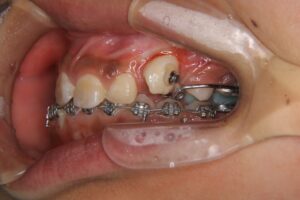

● 牽引治療の流れ

-

口腔外科で歯ぐきを切開し、埋伏歯の一部を露出させる

露出した埋伏歯に小さな装置(ボタン)を付ける

矯正装置のワイヤーとゴムの力でゆっくり口腔内へ引き出す

牽引には数ヶ月〜1年以上かかることもあり、治療全体の期間に影響します。